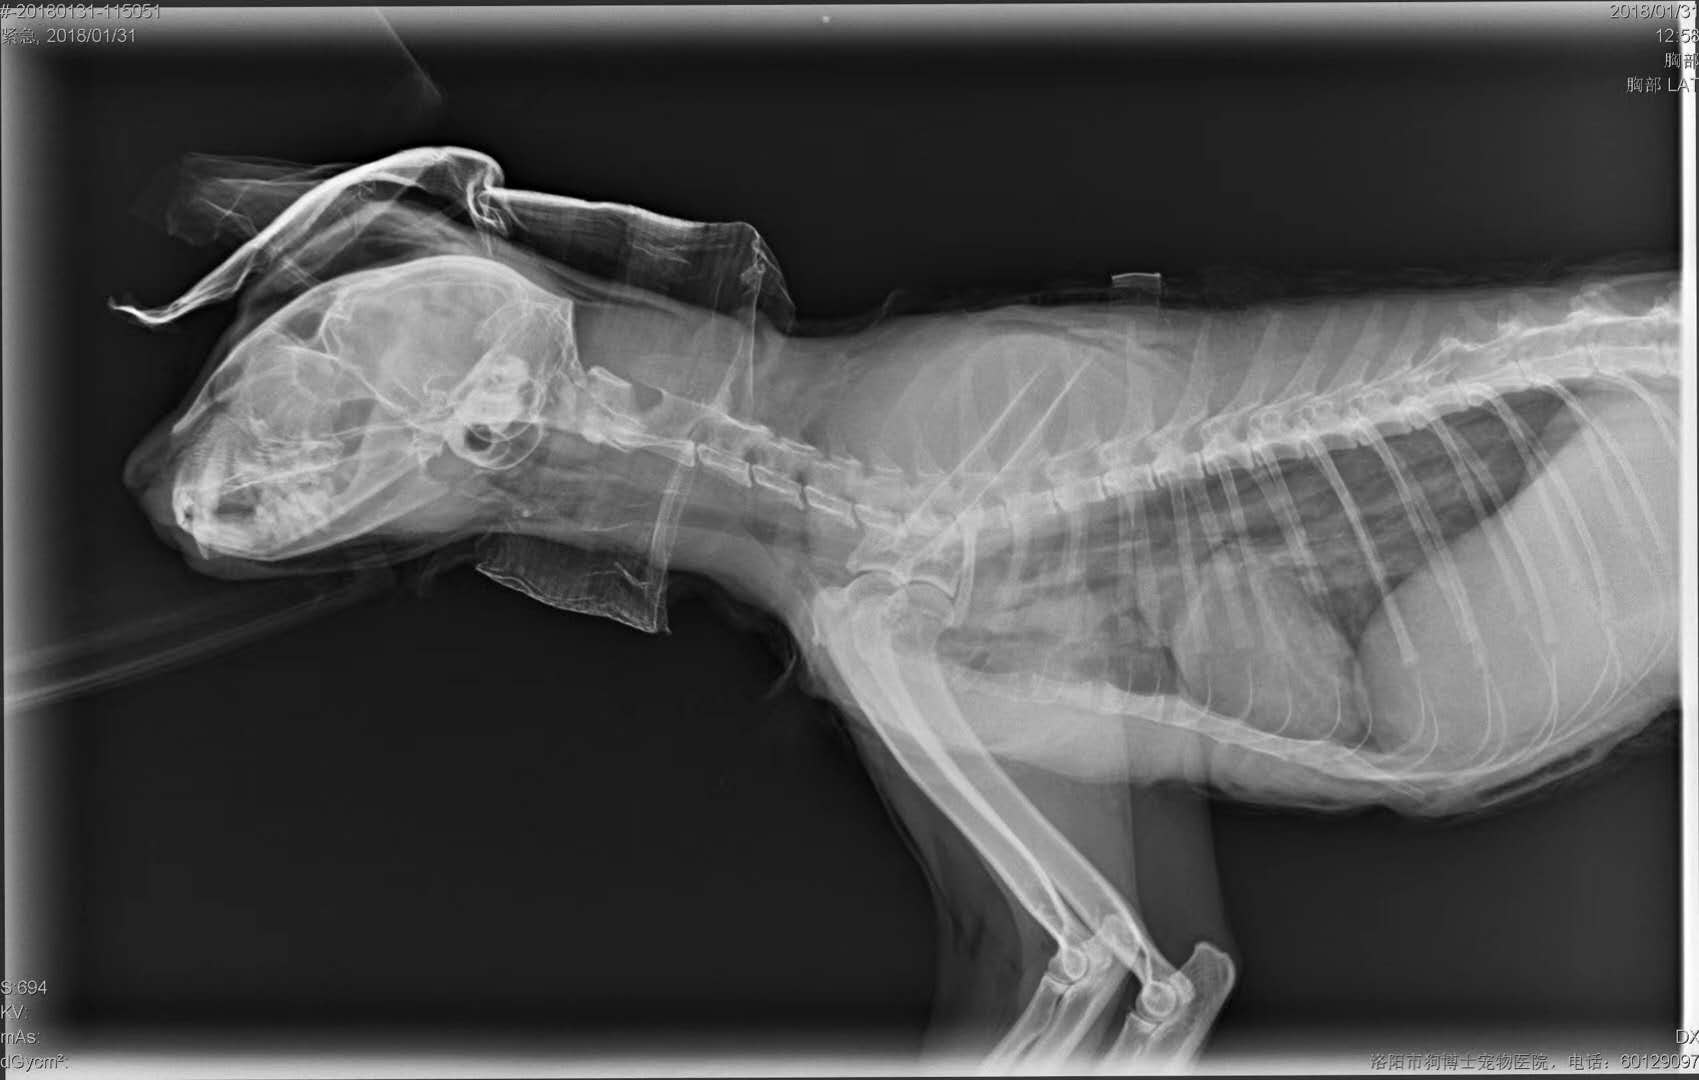

轉(zhuǎn)院全身氣腫病例治愈出院:暹羅貓,發(fā)財(cái),近期在其他醫(yī)院做的絕育手術(shù),術(shù)后出現(xiàn)全身氣腫(第2,第3張照片為原醫(yī)院拍攝),轉(zhuǎn)賬至我院,經(jīng)我院檢查發(fā)現(xiàn),在貓咪氣管入胸段,約有5.6mm大小孔洞,氣體延此孔泄露,并移行到頸部背測,接入皮下疏松結(jié)締組織,進(jìn)一步擴(kuò)散至全身。推測可能與絕育手術(shù)呼吸麻醉時(shí)氣管插管不當(dāng)有關(guān)。我院采取壓迫保守療法,住院10天,痊愈出院。PS:寵物主人選擇醫(yī)院時(shí),一定要慎重,就診時(shí)關(guān)鍵是大夫水平,其他是次要因素。